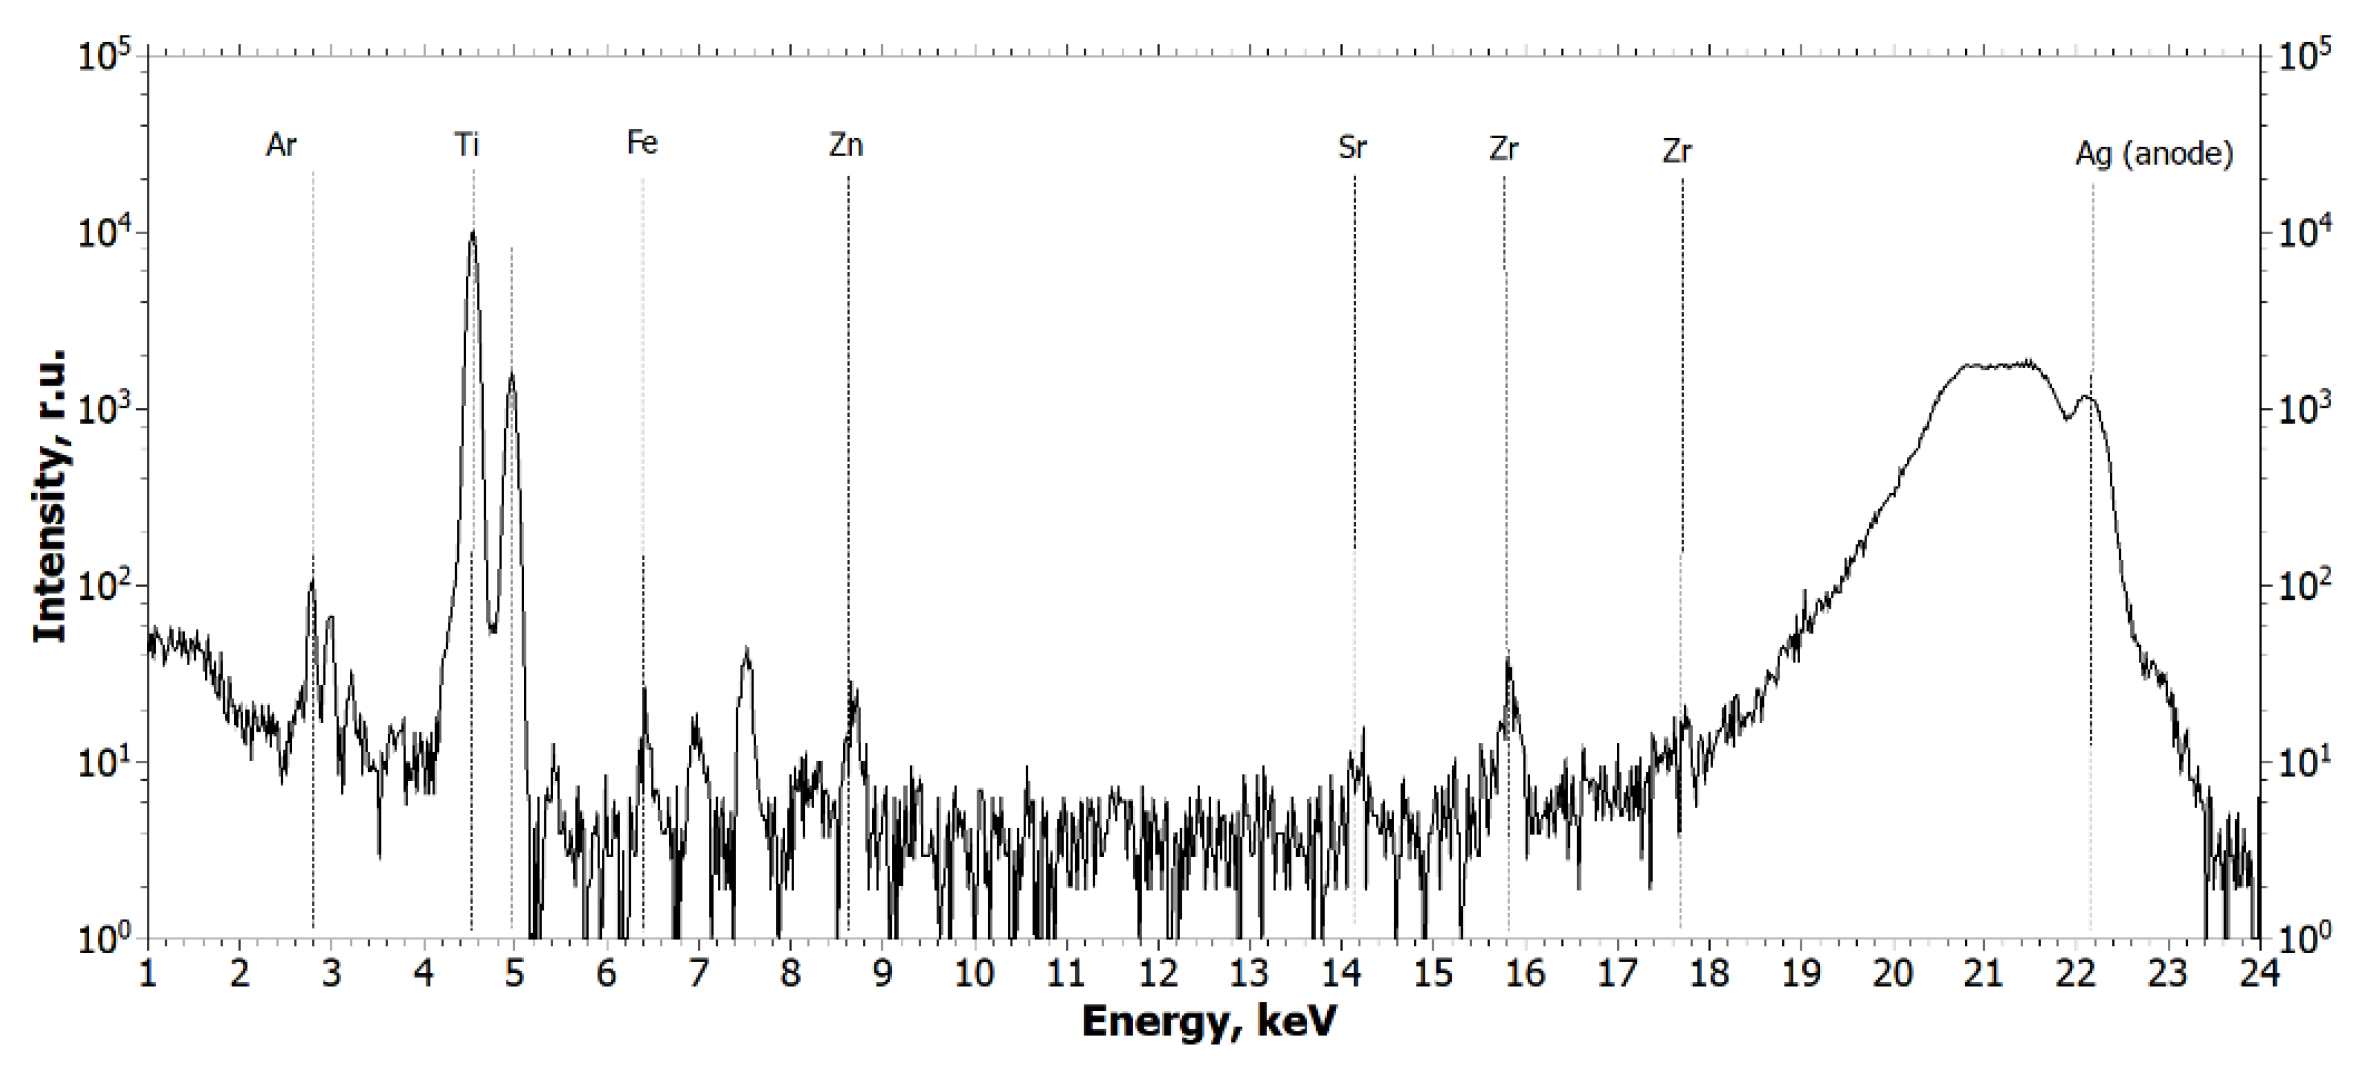

2.1.1. Results of X-ray and Electron Microscopic Studies

4.3. X-ray Fluorescence Analysis (XRF)

- Ag tube (focus size 10 × 1.0 mm), 40 kV × 40 mA mode;

- Monochromator—silicon (symmetrical), reflection (111);

- Wavelength—0.55 Å (E = 22.162 keV);

- Beam size—10.0 × 1.0 mm (slits adjustable);

- Detector—Amptek 123SDD (Amptek, Bedford, MA, USA);

- Exposure—1200 s per measurement.